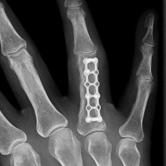

Röntgenbilder